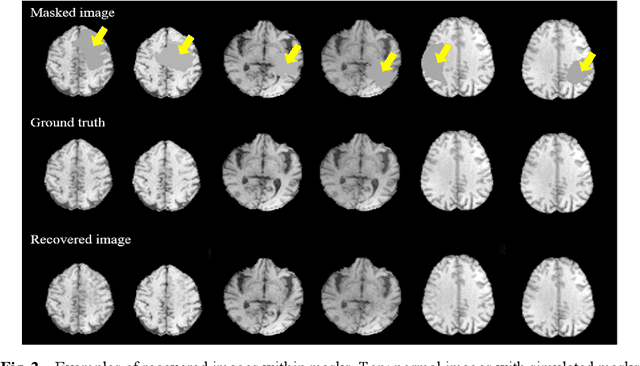

In brain tumor diagnosis and surgical planning, segmentation of tumor regions and accurate analysis of surrounding normal tissues are necessary for physicians. Pathological variability often renders difficulty to register a well-labeled normal atlas to such images and to automatic segment/label surrounding normal brain tissues. In this paper, we propose a new registration approach that first segments brain tumor using a U-Net and then simulates missed normal tissues within the tumor region using a partial convolutional network. Then, a standard normal brain atlas image is registered onto such tumor-removed images in order to segment/label the normal brain tissues. In this way, our new approach greatly reduces the effects of pathological variability in deformable registration and segments the normal tissues surrounding brain tumor well. In experiments, we used MICCAI BraTS2018 T1 tumor images to evaluate the proposed algorithm. By comparing direct registration with the proposed algorithm, the results showed that the Dice coefficient for gray matters was significantly improved for surrounding normal brain tissues.